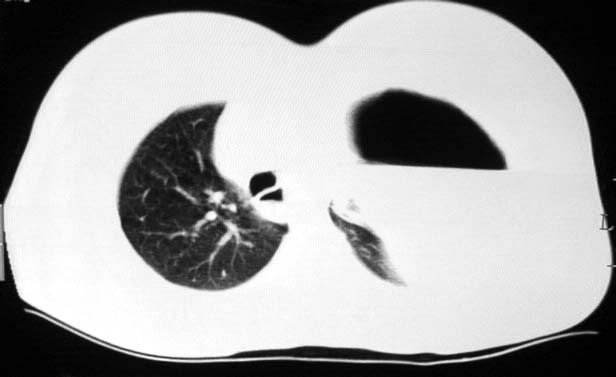

标题: CT5517:女性、24岁,反复胸痛、气促不能平卧半月。 [打印本页]

标题: CT5517:女性、24岁,反复胸痛、气促不能平卧半月。

左肺可见二个含气或液气的囊状影,左肺段支气管、左肺动脉显示不清,纵隔右移,考虑:左肺支气管肺囊肿,左肺发育不良,纵隔疝。

左侧气液腔与胃腔影相连,考虑膈疝。钡餐检查有助于诊断。

我看这是膈疝,在纵隔窗第六\\七幅图像上可见胃粘膜影,再者可见两个腔影,这在液气胸是不会有的.

液气胸 怎么会有2 个大腔?

还是个膈疝